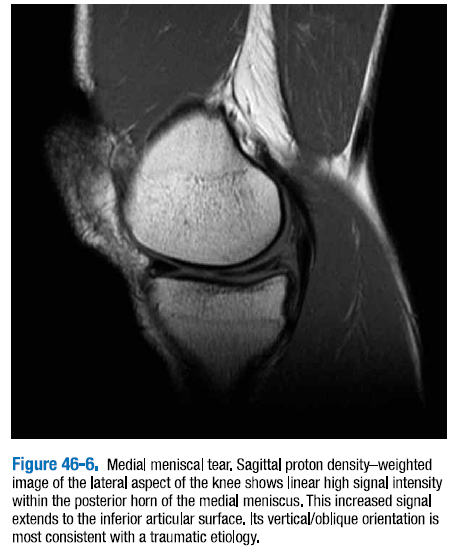

△ 그림 46-6. 내측 반월판 파열

무릎의 외측 시상면 양성자 강조 영상은 내측 반월판의 후각 내의 선형의 높은 신호강도를 보인다. 이러한 증가된 신호는 하방연골표면으로까지 연장된다. 수직/사선 방향은 대부분 외상성 병리와 일치한다.